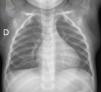

Destaca hipoventilación de hemitórax izquierdo, sin hipoxemia, ni distrés. En la radiografía de tórax presenta atelectasia completa del pulmón izquierdo, con hiperinsuflación del pulmón contralateral (fig. 1). La analítica sanguínea se encontraba dentro de los rangos de referencia.